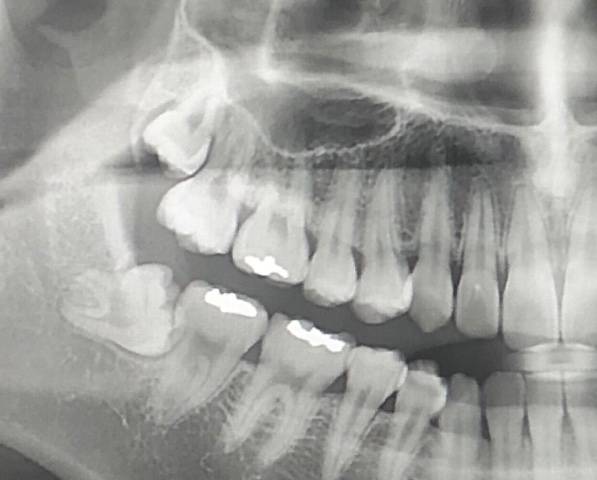

나 사랑니가 이렇게 나고 있는데 저 사진 찍은 게 석달이 넘었거든?? 그래서 계속 자라고 있어서 그런지 옆에 어금니도 아파 ㅠㅠㅠ 원래 이런거야? 아니면 어금니도 썩은걸까?? 금으로 떼운지 얼마 안됐는데😭

저거 매복이라서 저 사랑니가 옆에 어금니 밀어서 아픈거야!나도 충치인줄 알고 갔는데 사랑니때문에 그건거래ㅠㅠ그리고 뽑고나서 지옥이니까 참고해,,

저거 옆으로 누운거라 빨리뽑아야해

옆으로 자라면서 다른이를 미니까

나머지이빨에 안좋아

키키 나랑 똑같군.. 다행히 신경은 아슬아슬하게 피했고 난 오른쪽 아래 사랑니가 저랬는데 뽑고나니까 앞에 있는 어금니 옆구리가 조금 썩었다고 그러셨어! 뽑고 나니까 아물면서 잇몸이 그 부분을 덮었는데 시간이 지나면서 이 어금니가 더 썩게되면 나중에 뽑고 임플란트하라고 그러시더라